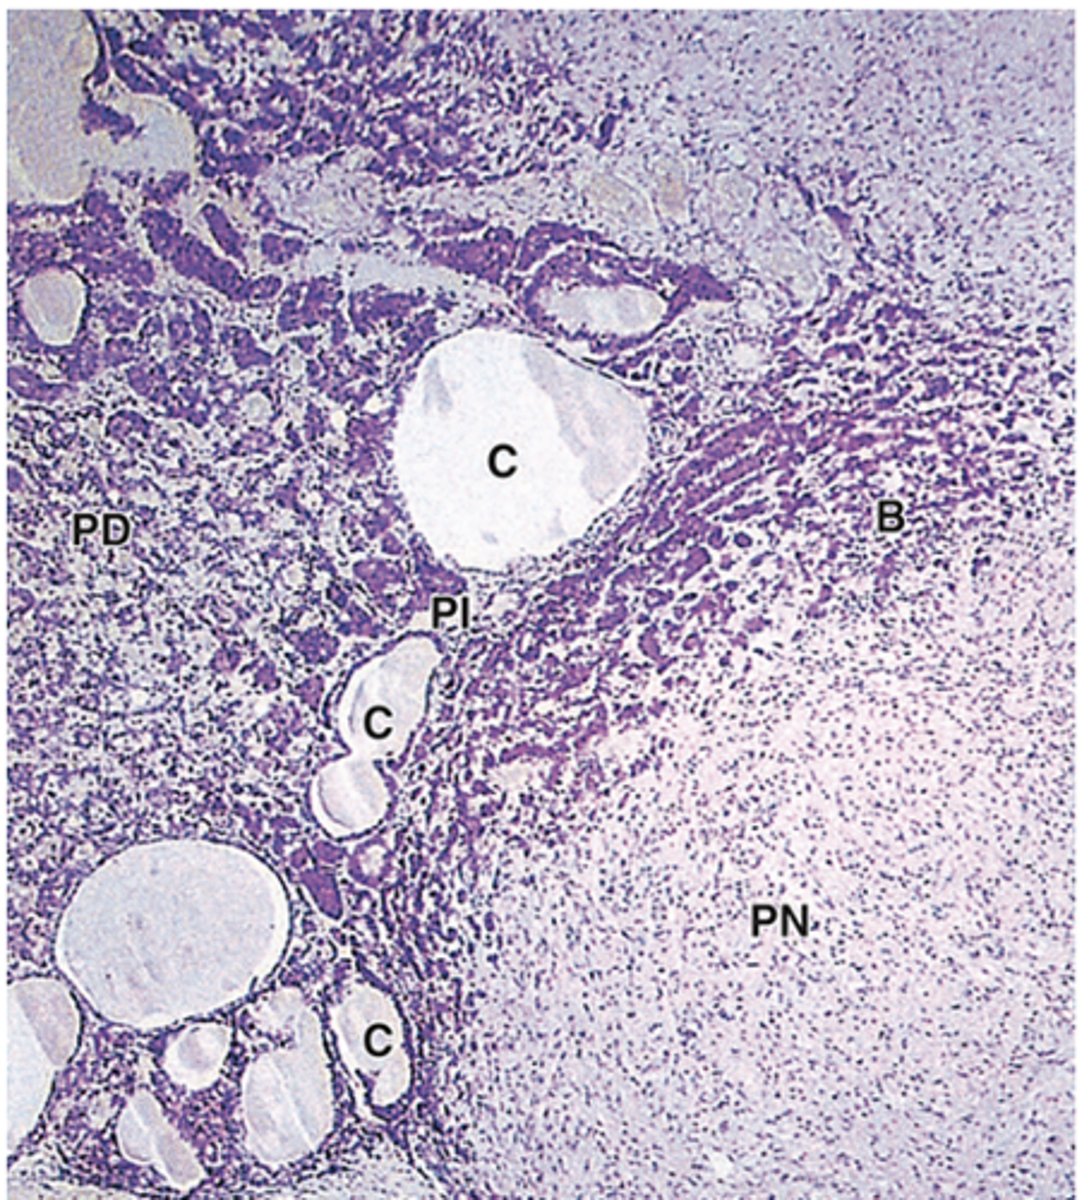

Where is the pars intermedia located?

A narrow region between the pars distalis and pars nervosa.

What are the main cell types in the pars intermedia?

1. Basophils (corticotrophs): produce MSH***

2. Chromophobes

3. Colloid-filled cyst: remnants of the Rethke pouch